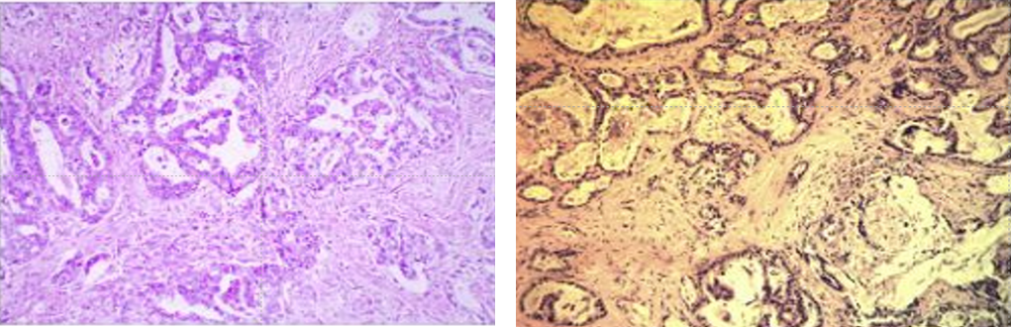

胃溃疡型中低分化管状腺癌淋巴结转移(图3左),肝内见中分化管状腺癌考虑为胃腺癌转移来源(图3右)。

图3 术后病理